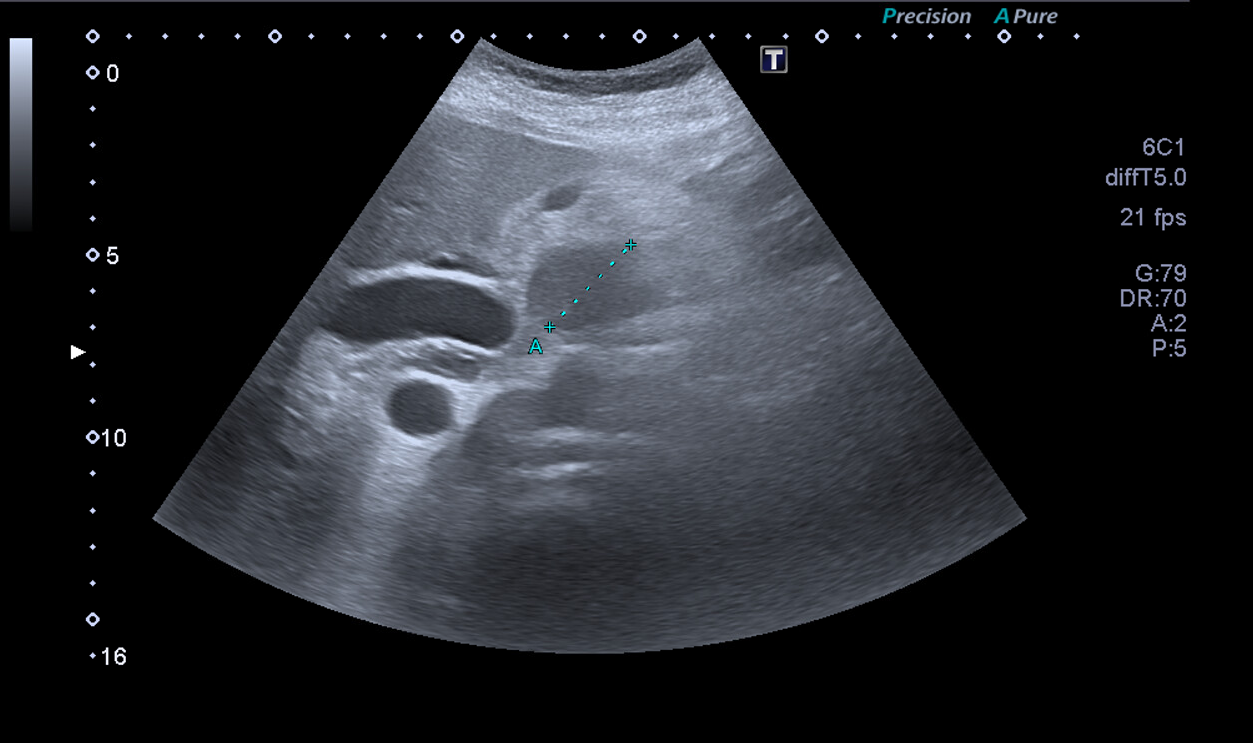

Ante la situación de dolor abdominal hacemos ecografía a pie de cama: se evidencia imagen redondeada de contenido heterogéneo de aproximadamente 38 mm, con dos imágenes redondas anecoicas en su interior en cabeza de páncreas. Restos de la exploración ecográfica sin alteraciones.

Juicio Clínico: Imagen redondeada de contenido heterogéneo de aproximadamente 38 mm.